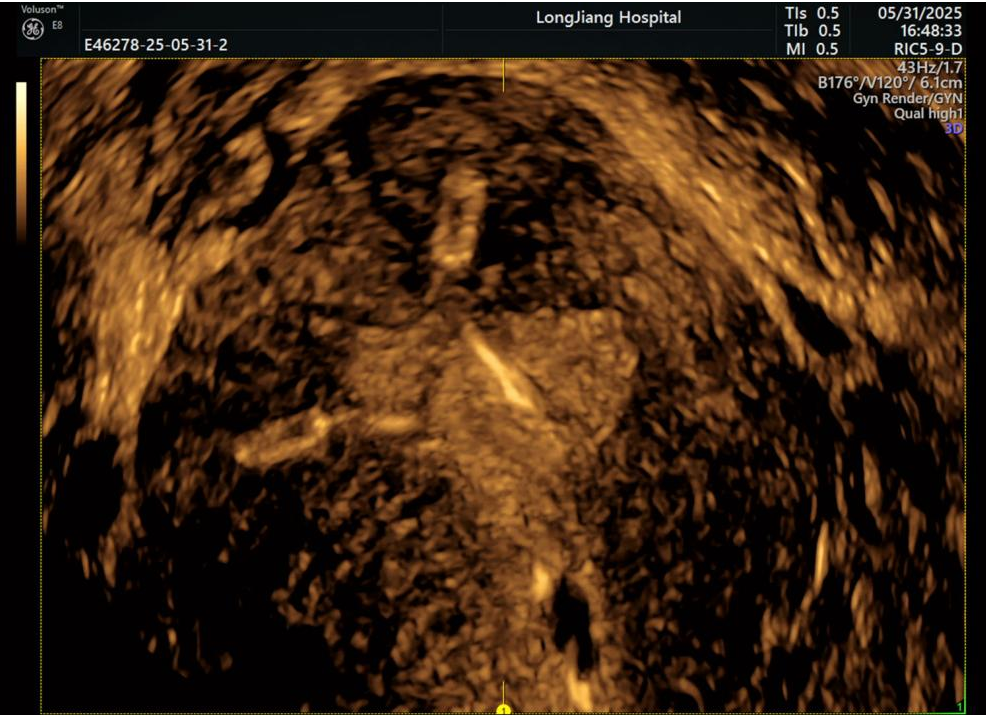

(不完全性纵膈子宫)

2. 看看“天鹅绒地毯”好不好:子宫内膜就是宫殿里软软暖暖的地毯啦!三维超声能看清地毯的厚度、均匀不平整?有没有小息肉(地毯上凸起的小疙瘩)?或者粘连(地毯黏在一起了)?